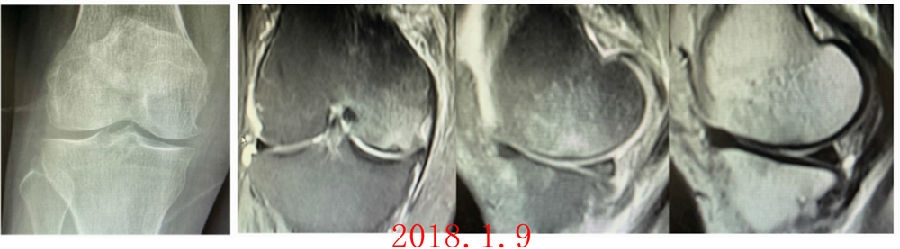

病例1:女,65岁,主诉右膝关节内侧疼痛1周。2018年1月X光未见右膝骨质异常,MR检查见股骨内侧髁骨坏死,半月板相对突出百分比(RPE)28.99%,关节线会聚角1.4°。

予切开行克氏针钻孔减压,口服消炎止痛药物、钙剂及骨化三醇,不负重6周,后改部分负重至3个月。2018年4月复查MR见骨髓水肿基本完全吸收,坏死区局限并修复良好,半月板相对突出百分比(RPE)32.08%,患者临床症状消失。

病例2:女,69岁,主诉左膝关节内侧疼痛1月余。2017年11月X光见右膝股骨髁负重区的软骨下区域出现了椭圆形透亮影,MR检查见股骨内侧髁骨坏死,合并内侧半月板外突和后角层裂,半月板相对突出百分比(RPE)25.32%,矢状位病变区域前后径为23.96mm,关节线会聚角6°。

予克氏针钻减压,消炎止痛药物口服、静滴唑来膦酸钠注射液,避免负重6周,后改部分负重至3个月,患者依从性差。2018年1月复查MR见骨髓水肿少许吸收,坏死区扩大,半月板相对突出百分比(RPE)33.53%,矢状位病变区域前后径为26.89mm,患者仍有膝关节疼痛症状,建议行手术治疗,患者拒绝手术后失访。